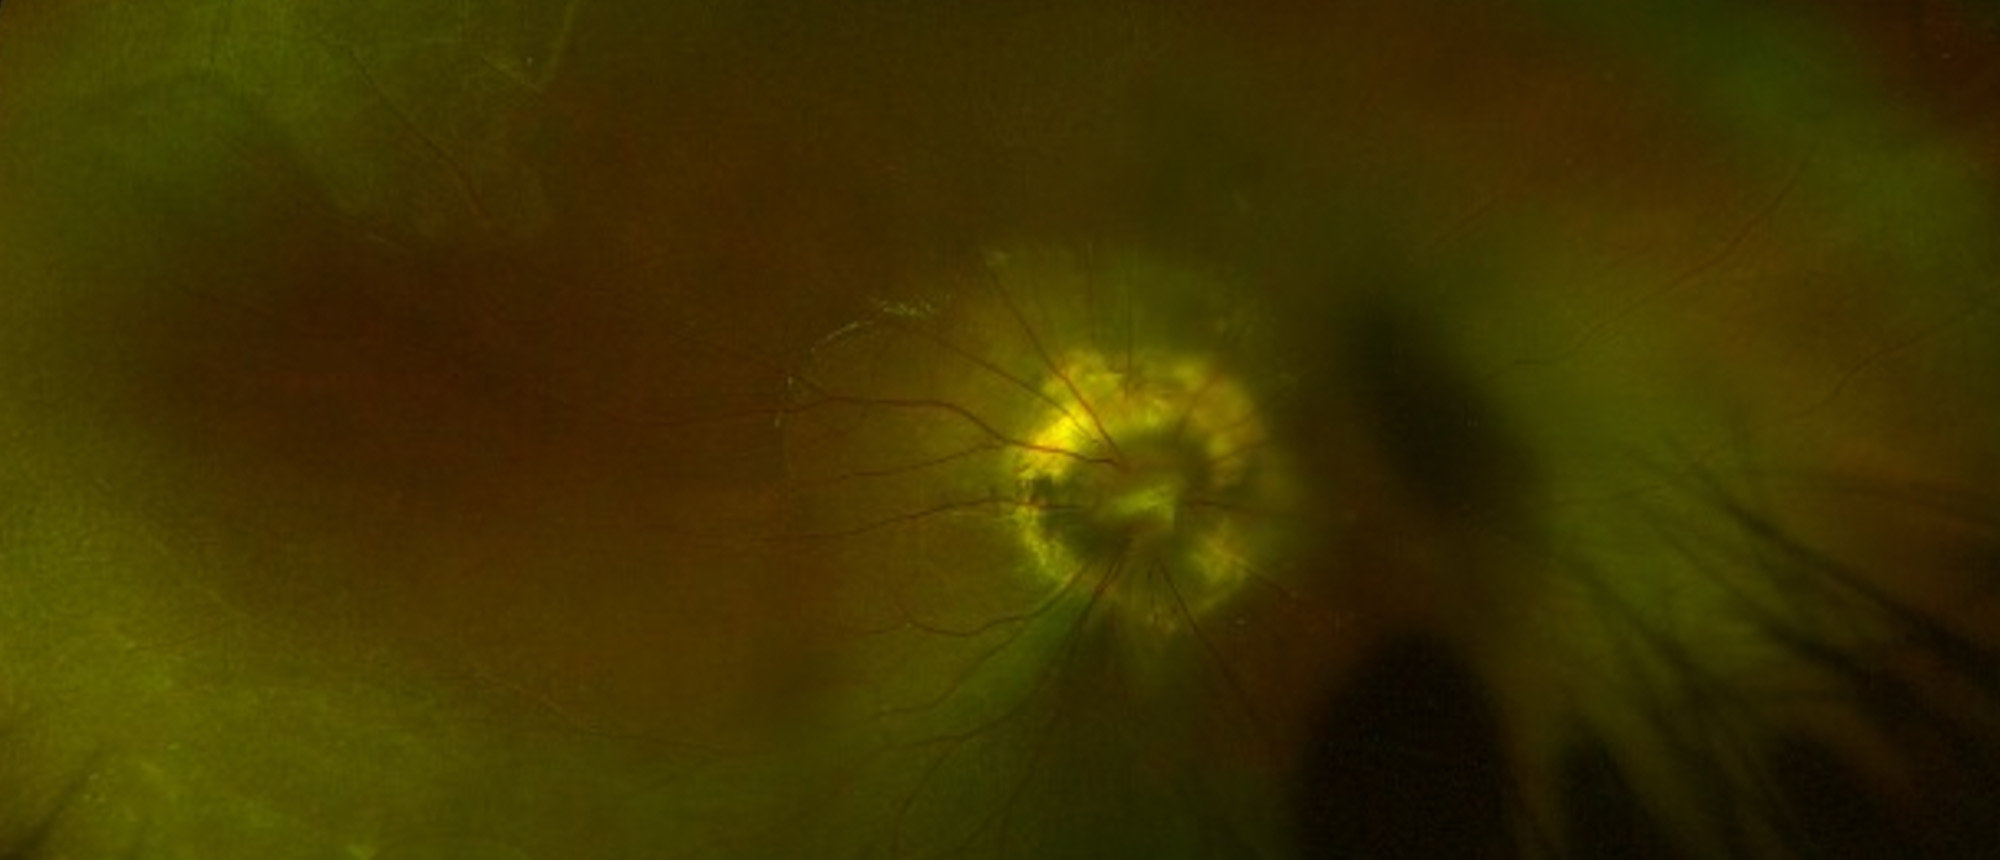

Morning Glory Disc Anomaly A child presented for evaluation of chronic poor vision of her right eye. Fundus exam showed an excavated nerve with peripapillary chorioretinal pigmentation, overlying central glial tuft, radial vessels, and inferior serous retinal detachment. Findings were consistent wi…